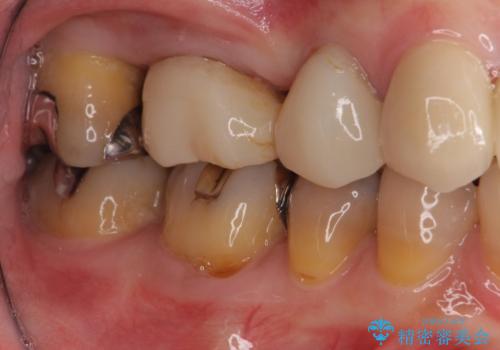

- 歯磨きの度に奥歯から出血があることを気にして来院された患者様です。

咬み合わせにより発現した歯周ポケットに汚れがたまり、歯周病のような状態になってしまっていました。